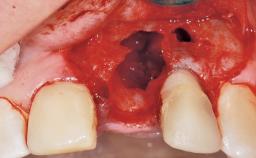

Late Flapless Placement of an Implant in a Maxillary Left Central Incisor Site

A 39-year-old male patient presented with a chief complaint of discomfort and gingival discoloration around his maxillary left central incisor. He was in good general health and was a non-smoker. His past dental history was significant because of the traumatic fracture of tooth 21 in a sporting accident at age 13. Initial dental treatment included endodontic therapy and a full-coverage restoration. The patient became symptomatic 5 years later, when structural failure of the tooth resulted in the dislodgment of the crown. Endodontic retreatment, apical surgery, and post-and-core restoration were performed.

Bone Augmentation Horizontal|Staged

Bone Volume Deficient horizontally, requiring prior grafting